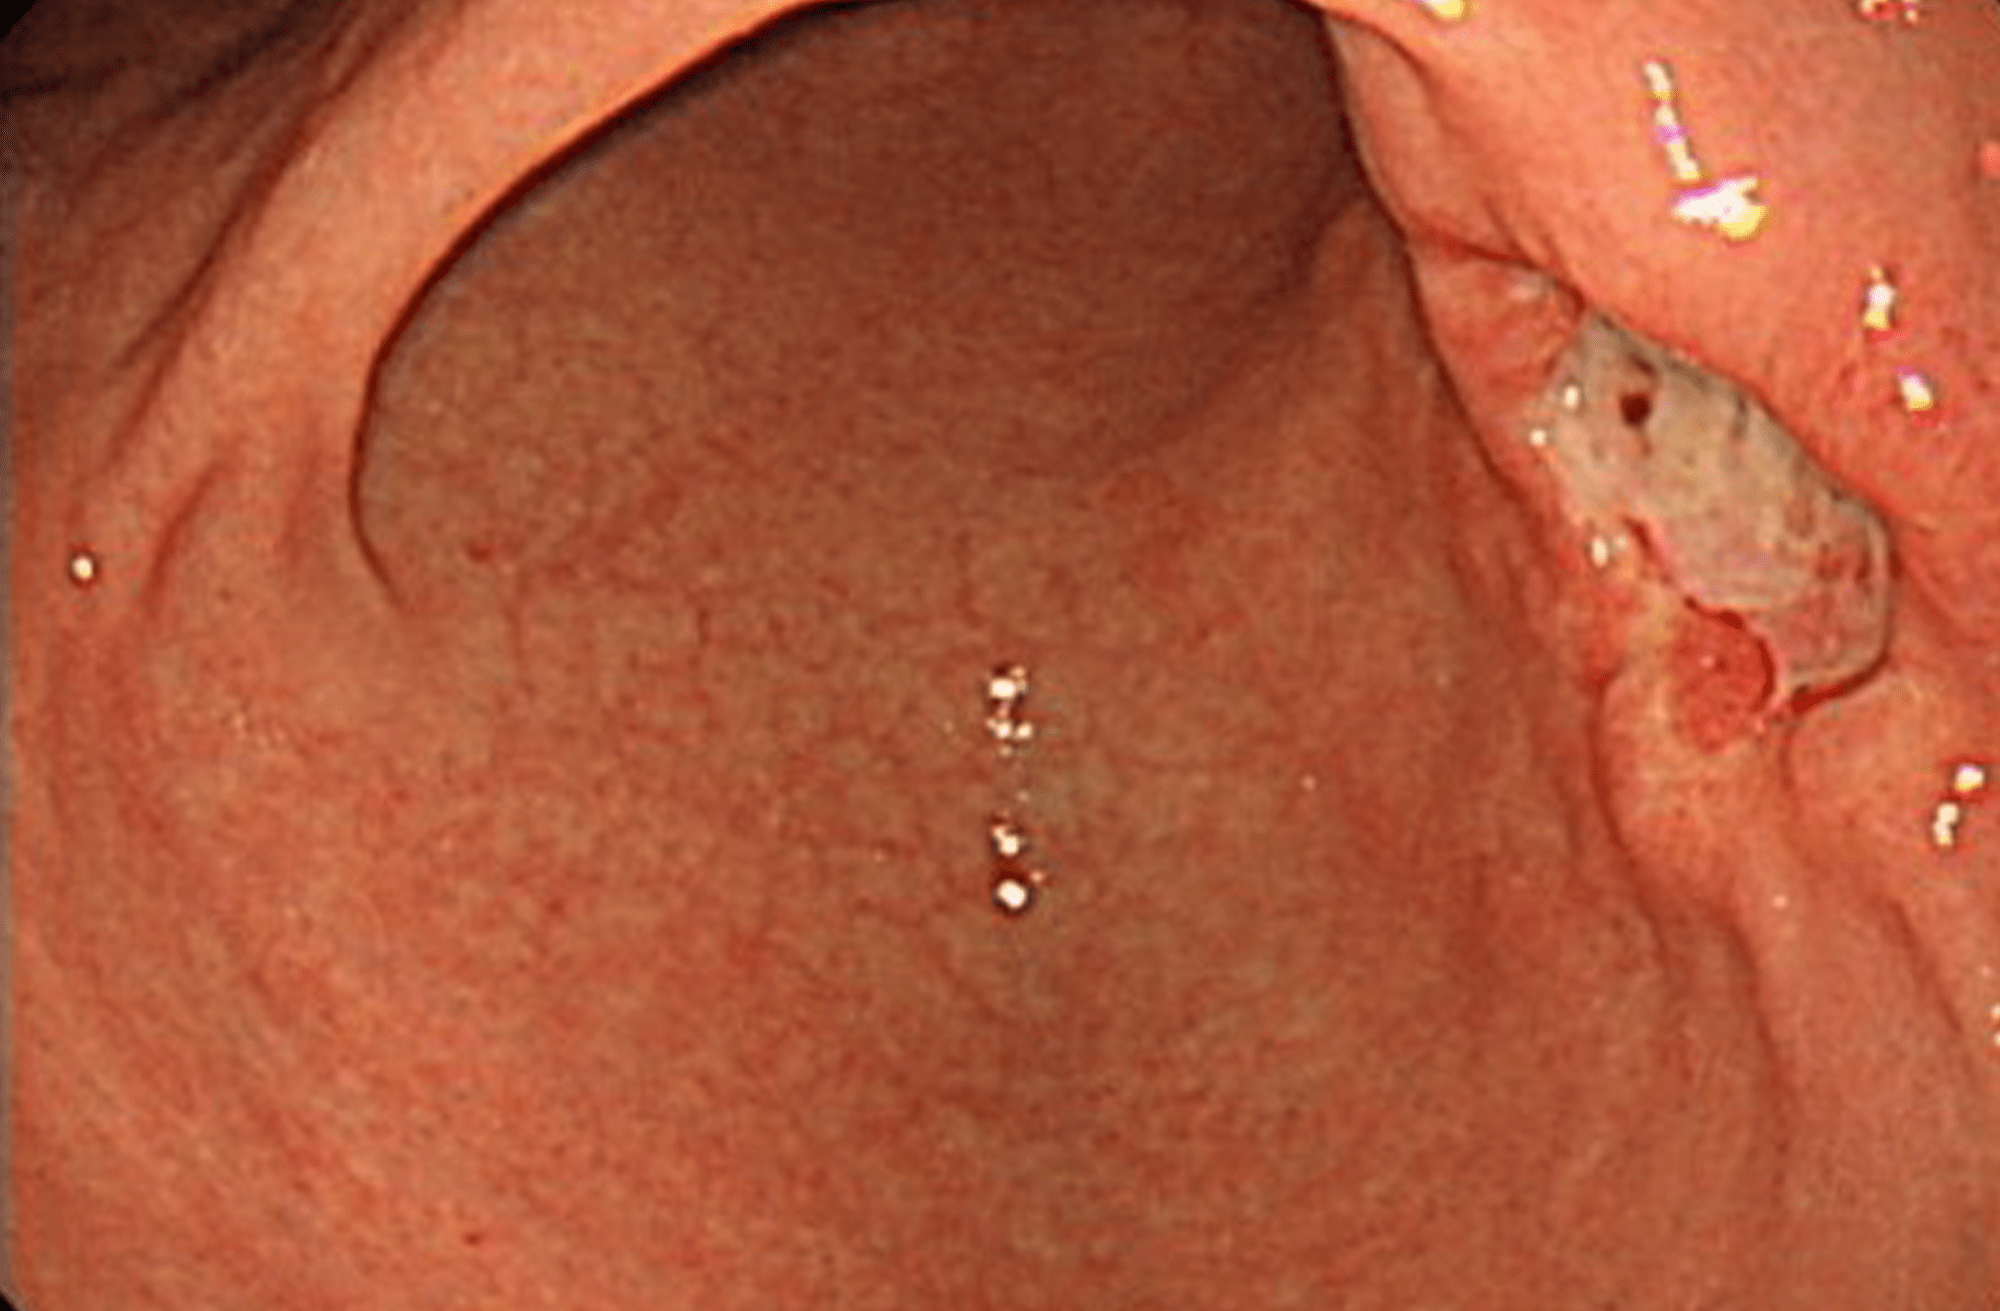

胃カメラ検査とは、口または鼻から細い胃カメラを挿入し、食道から胃、十二指腸までの粘膜を観察する検査です。これらの臓器の炎症や出血、ポリープや悪性腫瘍の有無や病気の程度などが診断可能です。必要に応じて粘膜組織を一部採取し、顕微鏡での病理検査も行います。検査時間の目安は5~10分程度です。

胃カメラ検査では様々な消化器疾患を診断することが可能です。下記は胃カメラ検査で診断できる代表的な病気です。